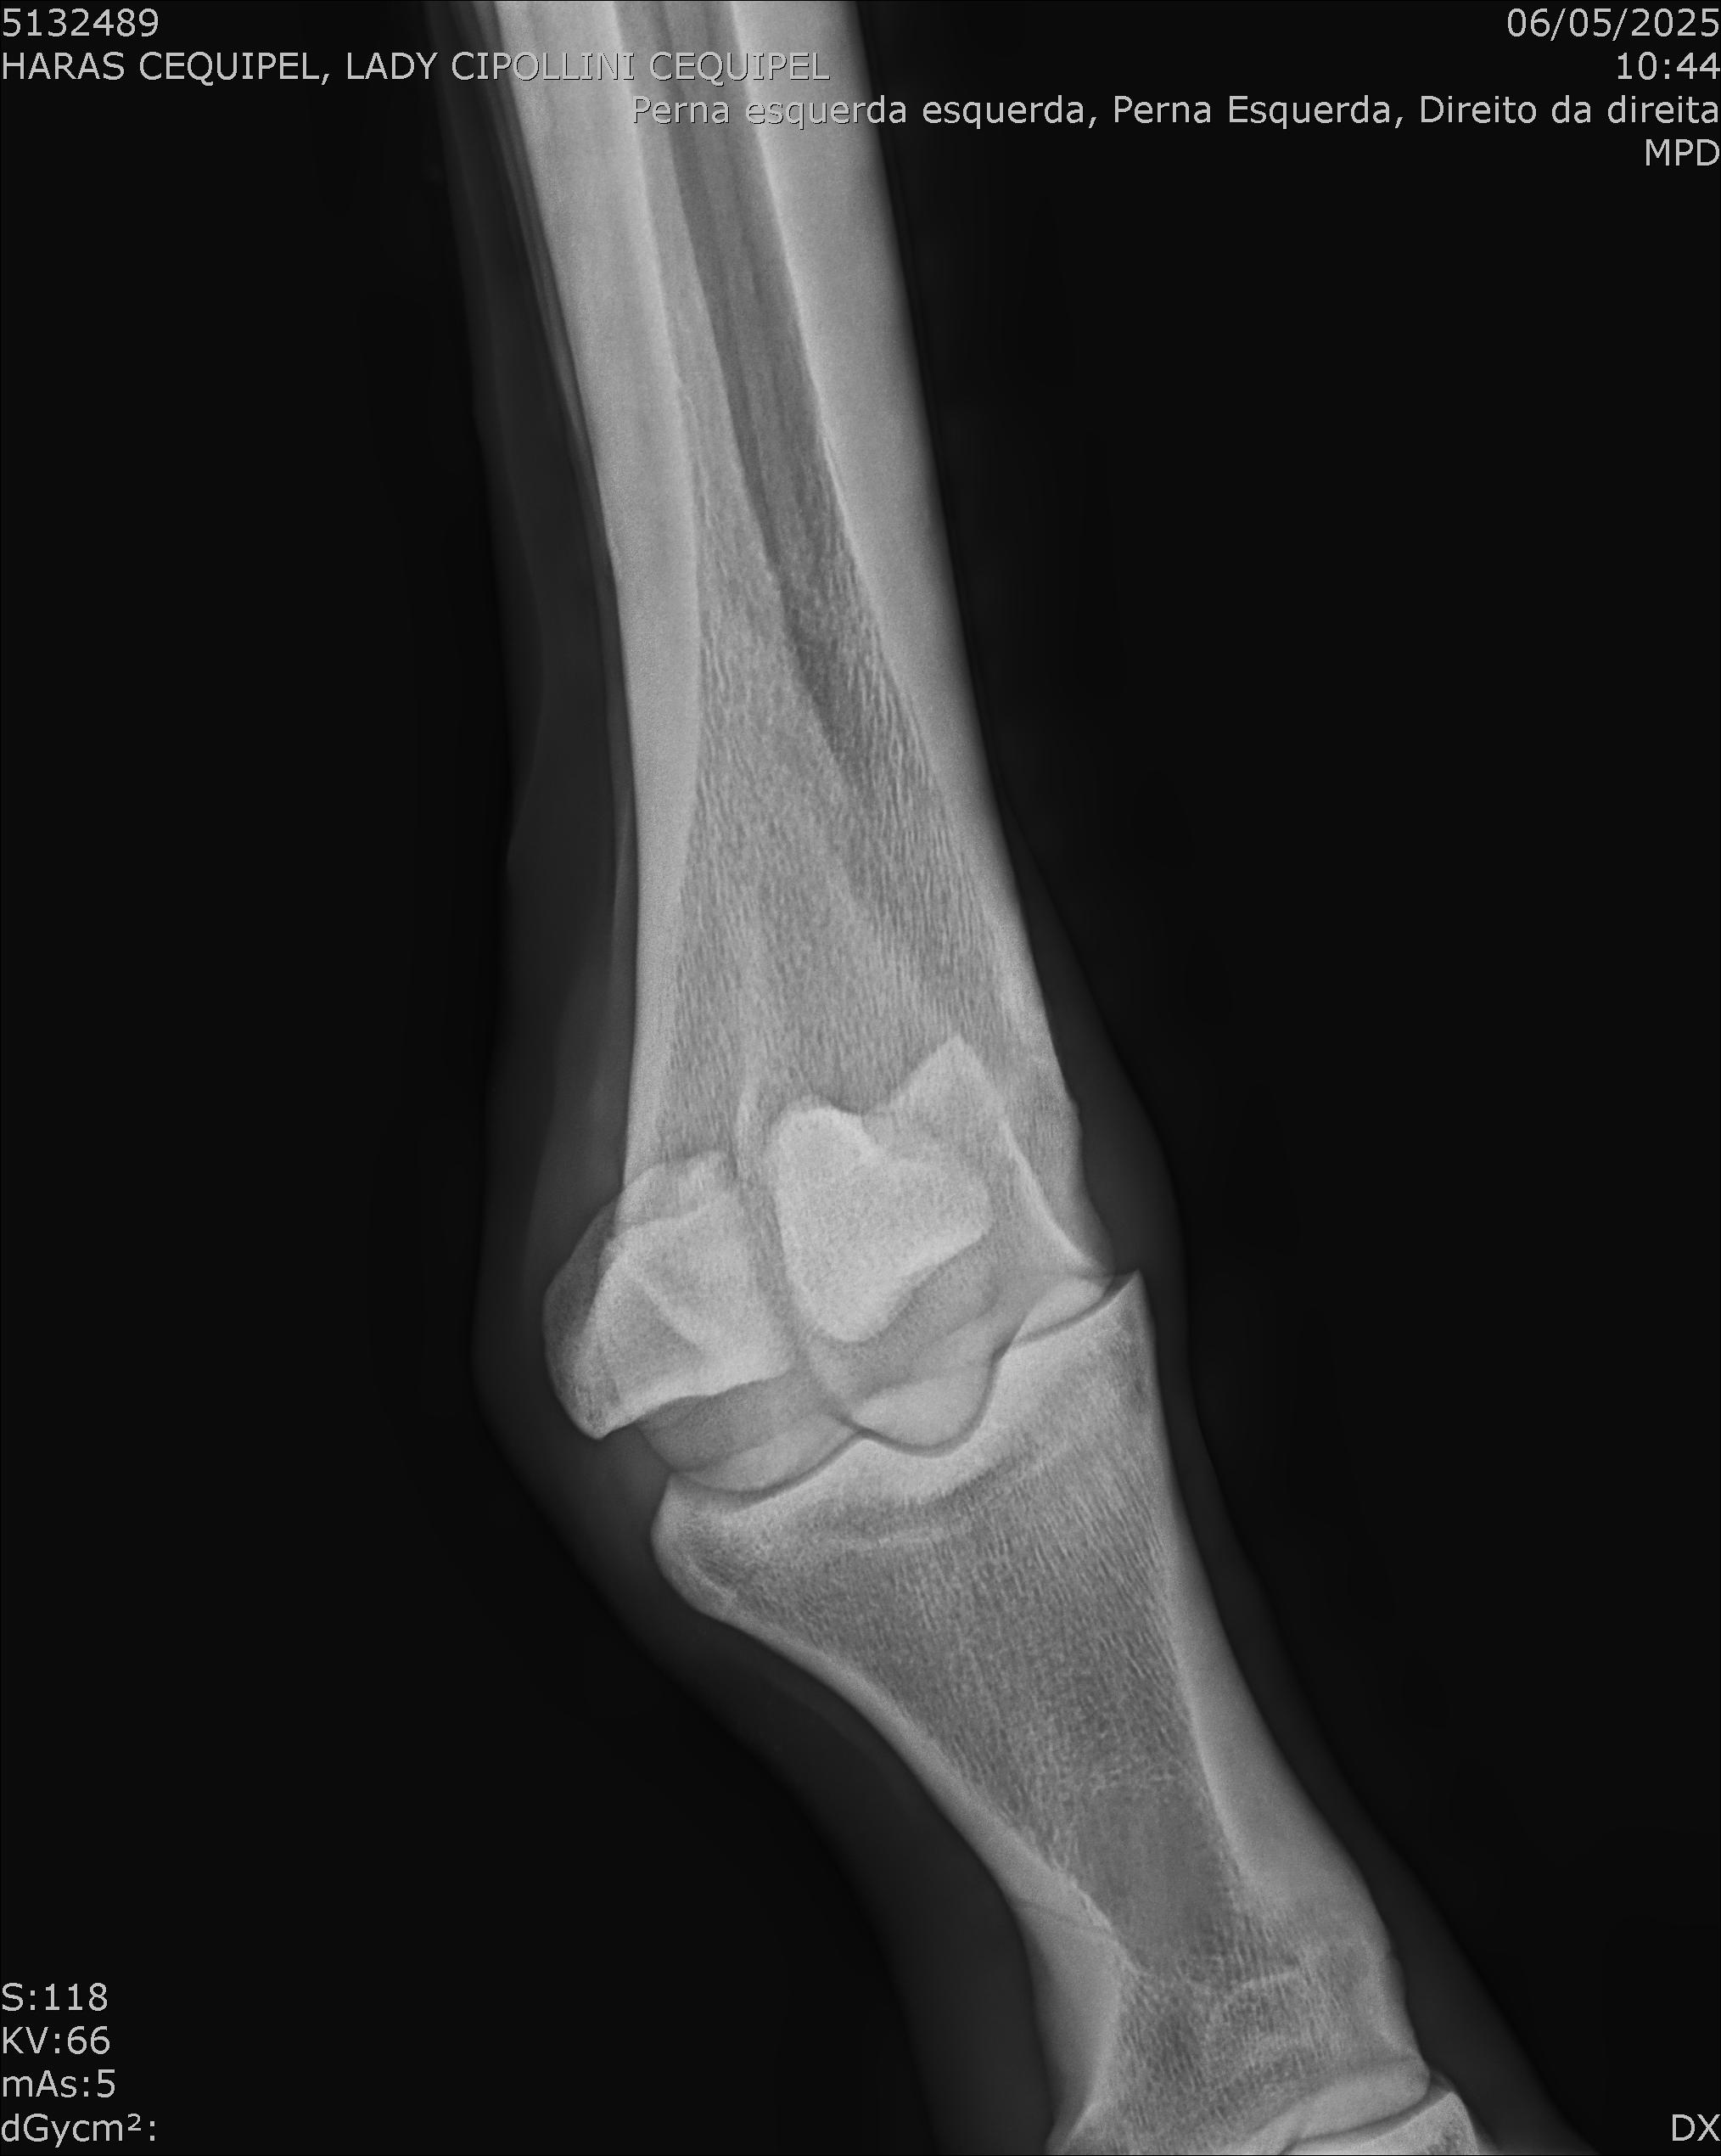

:: RAIOS-X DO LOTE